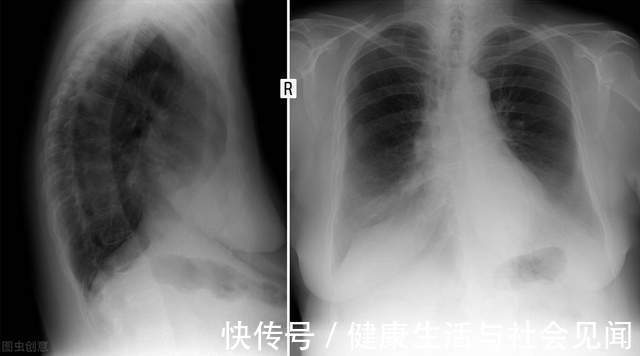

大量的研究数据显示,营养与免疫息息相关,营养不良的个体更容易遭受细菌、病毒的感染。此外,慢性或严重感染会进一步引发个体出现营养不良或营养状况的恶化,从而形成恶性循环,导致不良临床结局。早在2019年,世卫组织—中国冠状病毒病联合特派团的报告中指出:新冠肺炎的临床病程在老年群体以及与营养相关的疾病,如:糖尿病、高血压、癌症等慢性病患者中更为严重。因此,在新冠肺炎疫情防控常态化的今天,肿瘤康复期患者还需要格外关注自己的饮食和营养状况。